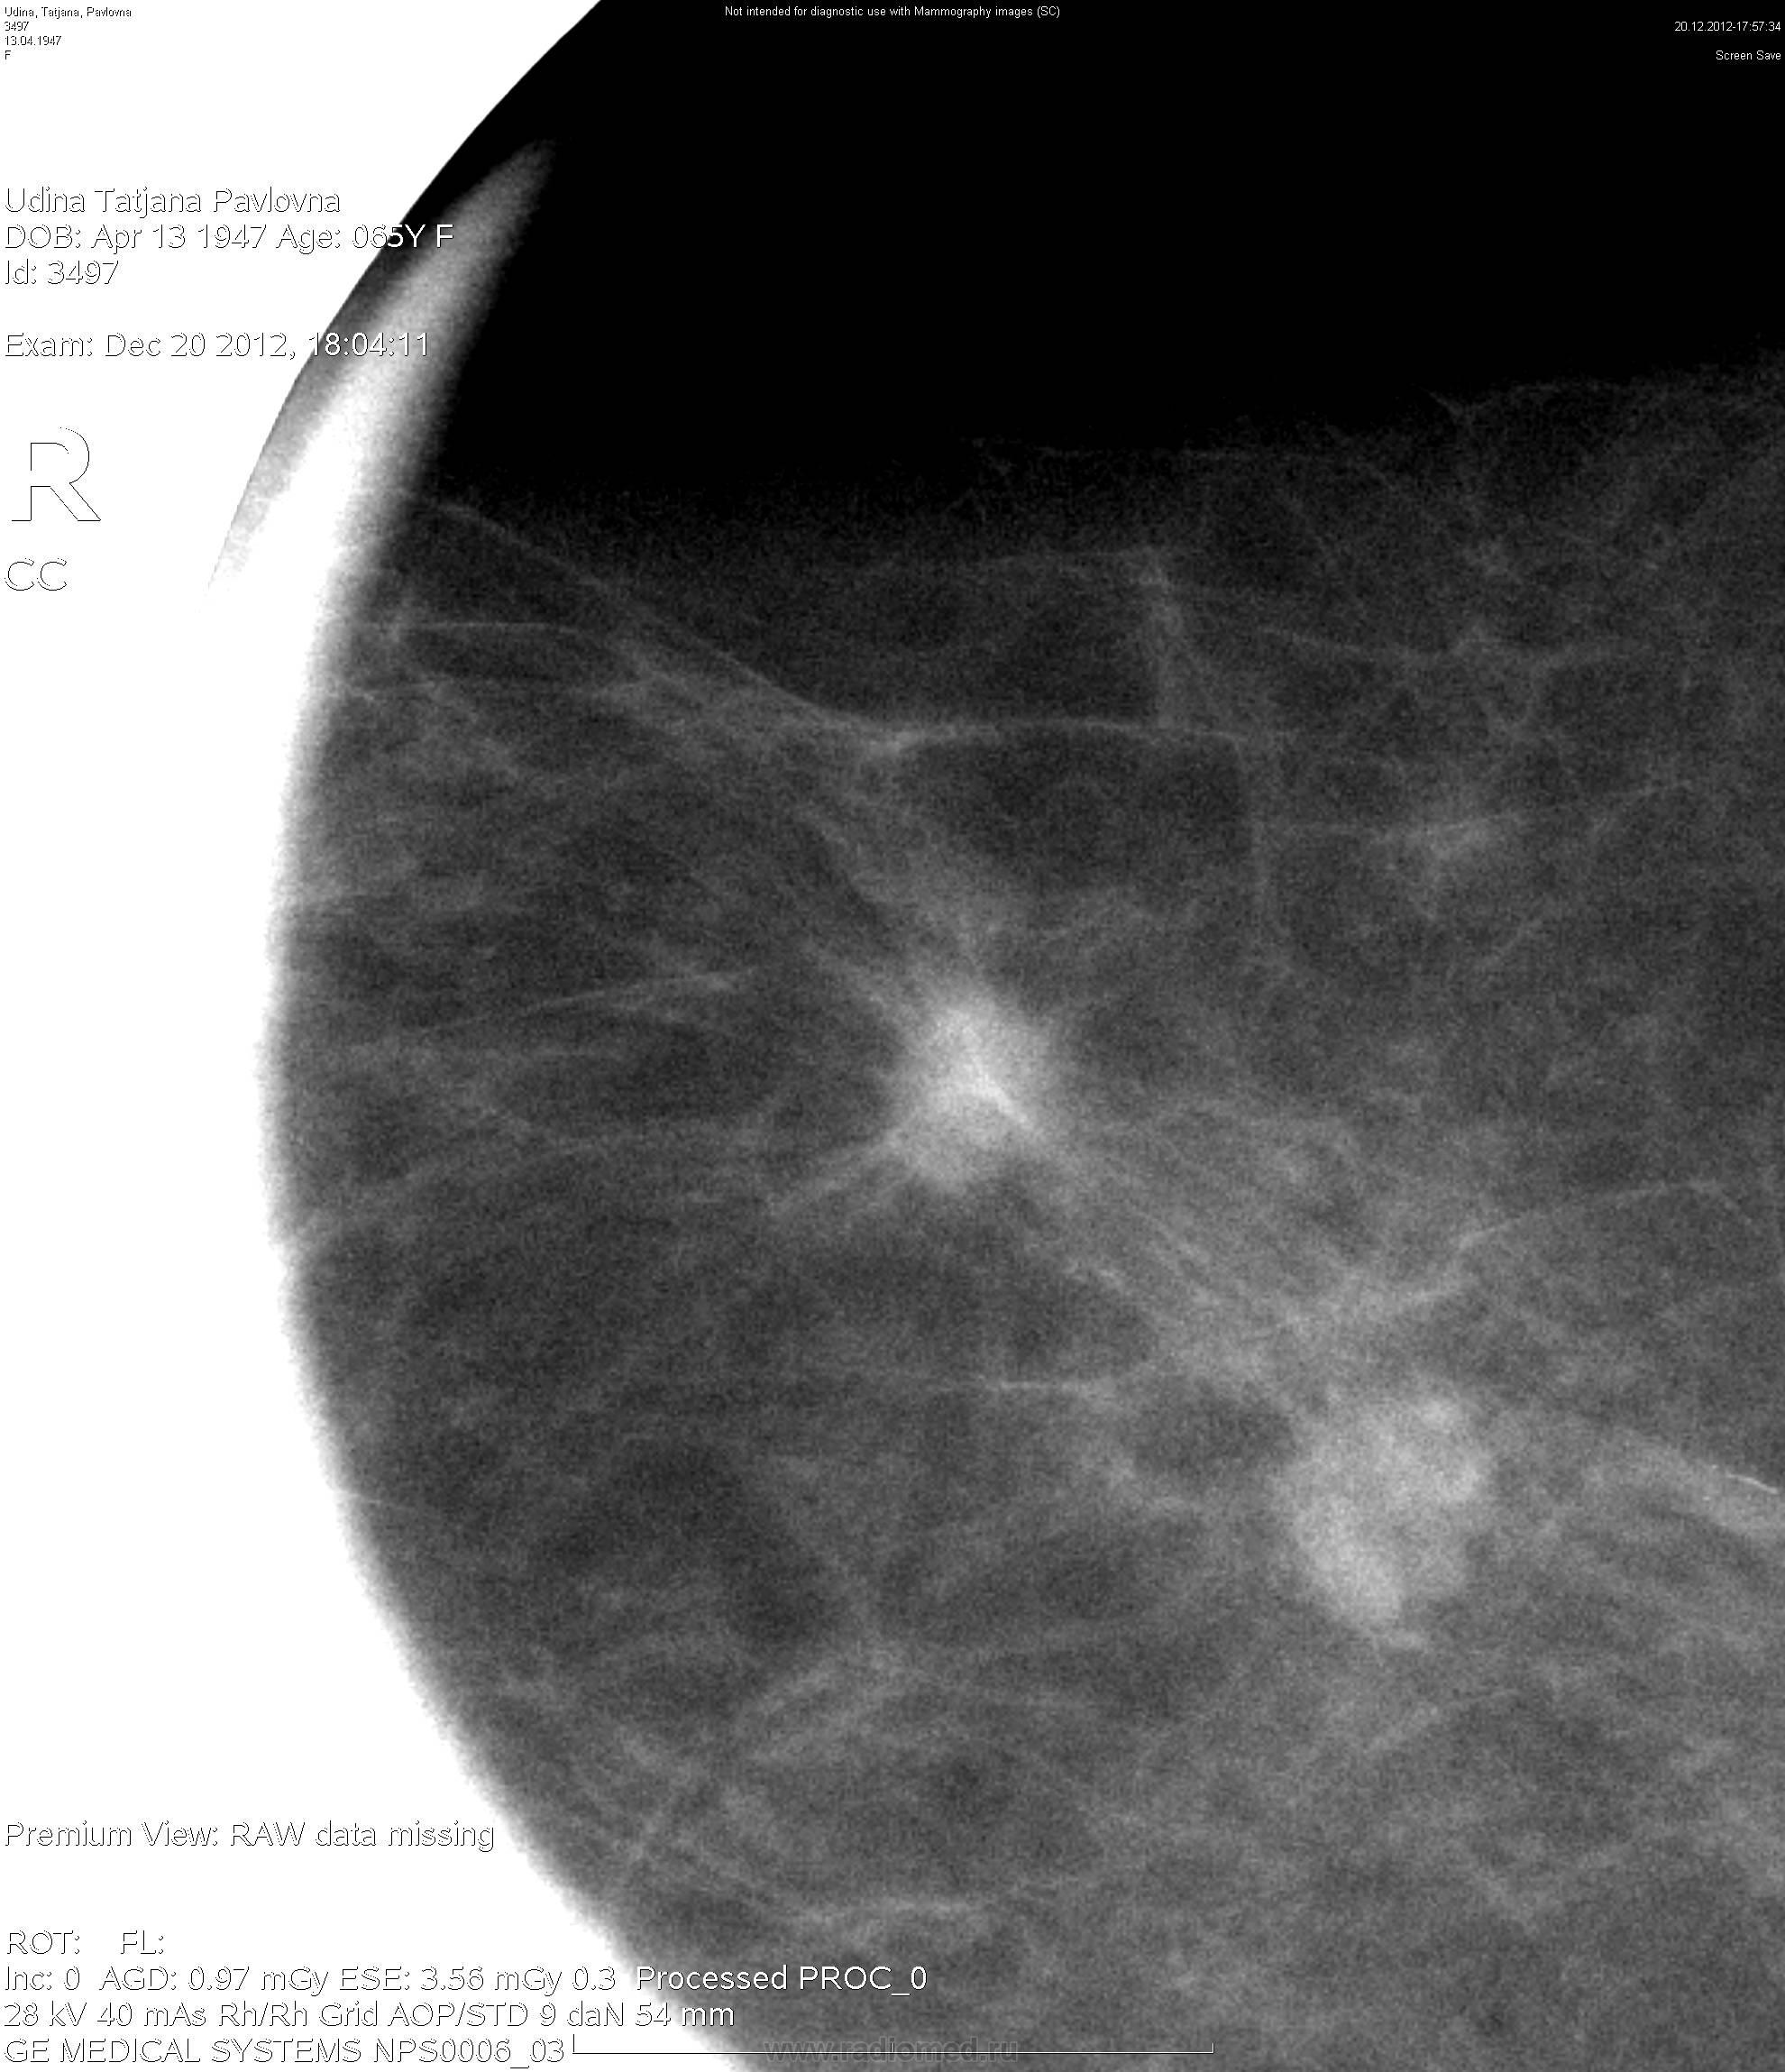

Маммография и ее роль в диагностике фиброаденомы молочной железы

Маммография - это рентгенологическое исследование молочных желез. Оно позволяет выявить различные изменения в тканях, включая фиброаденому. На маммограммах можно увидеть структурные особенности опухоли и отследить ее динамику во времени.